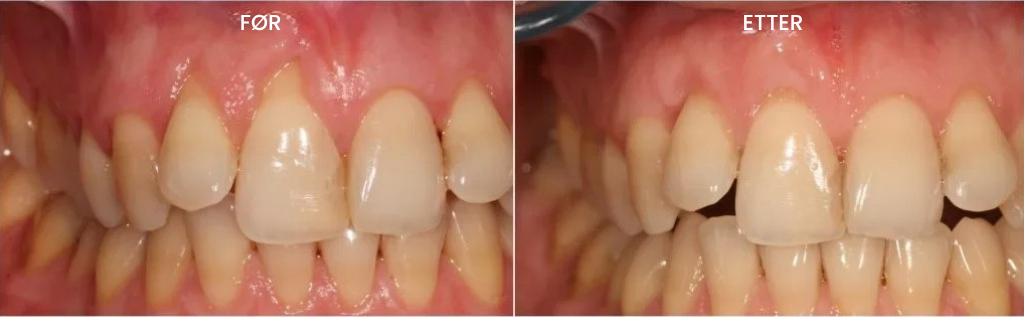

Da dr. Haughland presenterte funnet for kolleger, var mange skeptiske."De sa at tannkjøttvev ikke kunne vokse tilbake naturlig. Men så viste jeg dem de kliniske bildene av pasientene mine. Resultatene var ubestridelige."

I løpet av få måneder utviklet dr. Haughland formelen ferdig, og skapte det som nå kalles Teeth Repair Gel den første ikke-kirurgiske løsningen som faktisk reverserer tannkjøtt-tilbakegang, i stedet for bare å behandle symptomene.

Denne gelen har vunnet flere internasjonale priser, inkludert Årets 2025 Pris for Fremragende Innovasjon innen Tannhelse, og verdsettes av tannleger som en effektiv behandling som STOPPER og REVERSERER tannkjøtt-tilbakegang – med synlige resultater etter bare ÉN UKES bruk!

Allerede etter din første uke med Teeth Repair Gel vil du forstå hvorfor kundene våre kaller det “livsforandrende”.